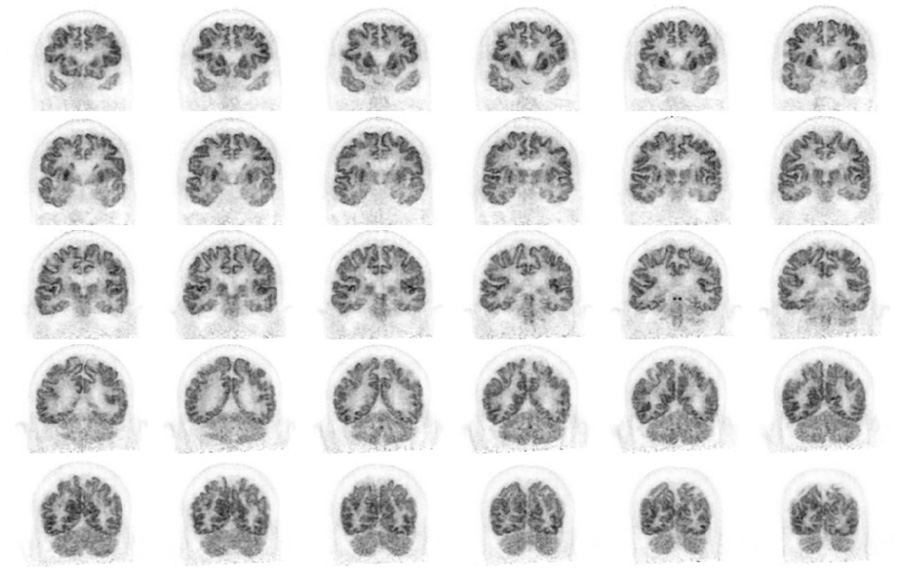

Head / Case1 : FDG

Coronal

- Imaging protocol

- Injected dose: 2.87 MBq/kg, 18F-FDG

- Uptake time: 42 minutes

- Scan time: 30 minutes